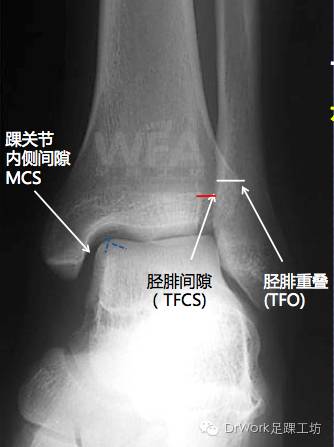

正位片

• TFCS<5mm

• TFO>5mm

复位后与健侧对比可显著提高复位准确率

• 健侧

• 患侧